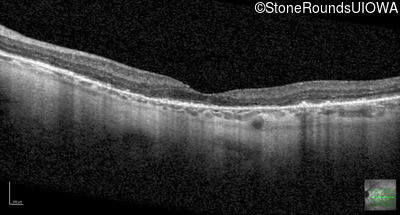

Optical Coherence Tomography - Right - 20/80

Exemplar / OCT Stack